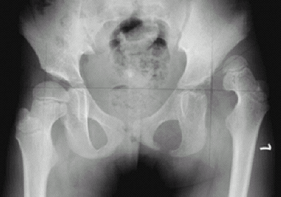

MRI and CT have only limited roles in usual cases of DDH (Fig. 2).

Fig.

2. DDH was not diagnosed until age 5 in this patient. Note the

extensive proximal migration and dysplasia of both femur and acetabulum.